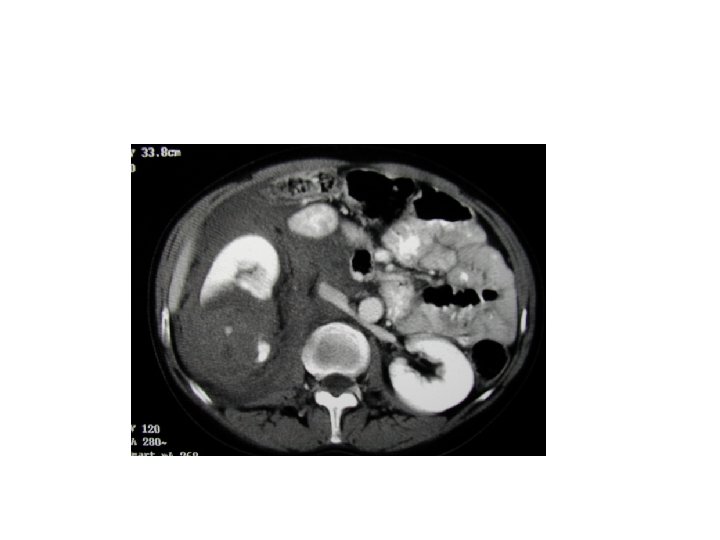

Whom to work up • Penetrating trauma: EVERYONE • Pediatric patients with microscopic hematuria. • Blunt trauma: Image with CT if: • gross hematuria • microhematuria plus shock • microhematuria plus acceleration/deceleration Mee et al. (1989) Hardeman et al (1987

Imaging of trauma patient with hematuria • CT preferred – With contrast – With “delayed” films (mandatory) – Why not get CT cystogram too? • Standard intravenous pyelogram (IVP): Forget it • “One Shot” intraoperative IVP – 2 cc/kg intravenous contrast – Single film at 10 minutes

Intraoperative One Shot IVP • Allows safe avoidance of renal exploration in 32% (Morey et al, 1999) • Highly specific for urinary extravasation • Confirms existence of the other kidney